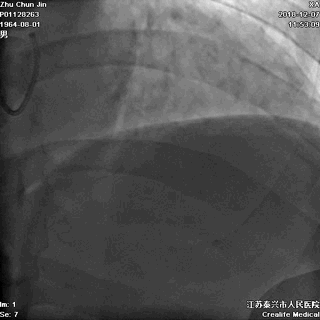

胸部透视,看看心影吧:

▲胸部透视见纵隔影似乎明显增宽!是夹层吗?

接下来是经猪尾导管行主动脉造影,还是行其它检查呢?